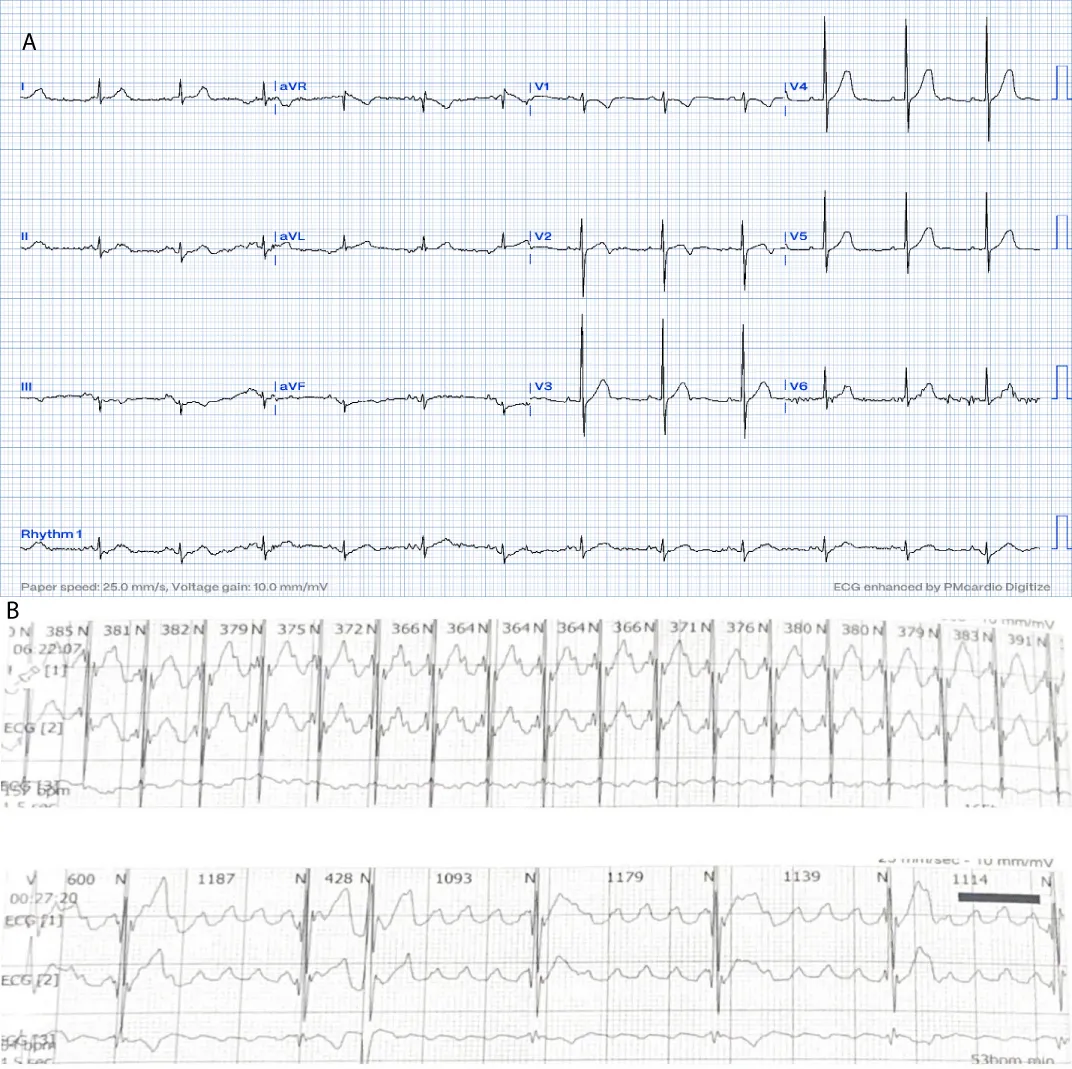

A 16-month-old child with no past medical history, referred for bradycardia. She was clinically asymptomatic except for poor growth consistent with weight and height below the third percentiles. Her ECG (Figure 1A) revealed left axis deviation, normal PR interval but with significant bradycardia indicative of Sinus Node Dysfunction (SND). Her echo revealed a small ASD but was otherwise normal. The Holter (Figure 1B) showed persistent atrial flutter (AFL), with variable degrees of block (2:1 - 6:1) and heart rates (HR) between 53-150 beats per minute (bpm). The average HR was 92 bpm despite being not on any atrioventricular nodal (AVN) blocking agent, raising concerns about intrinsic AVN dysfunction. The patient was admitted (Figure 2) for TEE to rule out intracardiac thrombi and subsequent cardioversion. She was successfully reverted to sinus rhythm, but remained bradycardic, and was started on low-dose Sotalol, at 1 mg/kg/ day, given the intrinsic conduction disease. Maternal ECG was normal, but a paternal one could not be obtained, and genetic testing was refused. Family history was otherwise unremarkable. Two months later, a follow-up Holter revealed counterclockwise AFL for which she was admitted and again cardioverted successfully. Sotalol was increased to 1.5 mg/kg/day. Over the next four months, two follow-up Holter ECGs (Figure 3) showed junctional and ventricular escape rhythms with rare sinus capture beats. Two months later, the patient came back with AFL and underwent successful cardioversion (Figure 4). The family was offered either pacemaker implantation or ablation, but initially refused both. At this point, the dose of Sotalol was increased to 2 mg/kg/day. One month later, the patient returned with persistent AFL, underwent successful cardioversion, and agreed to proceed with ablation. A zero-fluoroscopy, dual-catheter electrophysiology study (EPS) was performed using 7F Freezor™ Xtra cardiac cryoablation catheter (217F1 – 49 mm), at the age of 2 years and 10 months (9 kg). The EPS demonstrated cavotricupsid isthmus based typical AFL (proved with entrainment), and cryoablation of the isthmus resulted in termination of AFL (one application for 2 minutes per location, point by point across cavotricuspid isthmus). After ablation and while not on sotalol, the rhythm was predominantly junctional rhythm, but no recurrence of flutter was observed over the subsequent 12 months. The patient is currently approaching 4 years of age.

Figure 1: At the time of presentation. 1A: ECG shows bradycardia, left axis deviation, and negatively deflected P-waves in leads I and AVL suggesting left upper atrial focus.

Download Image

Figure 2: On the first admission. The ECG reveals positive sawtooth-like F waves in the inferior leads consistent with clockwise CTI-dependent AFL at 4:1 conduction. This was cardioverted to bradycardic sinus rhythm./p>